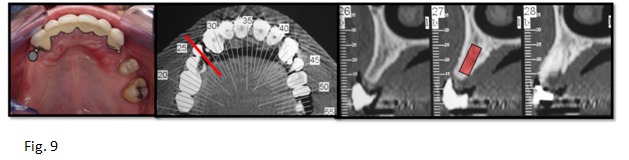

A partir del encerado se obtendrá la férula radiológica/quirúrgica, definida como “Dispositivo que relaciona el encerado diagnóstico y el estudio clínico y radiológico con el reborde desdentado en el momento de la cirugía, orientándonos sobre la ubicación óptima de los implantes”.

La férula debe diseñarse en función de la prótesis a realizar. La guía quirúrgica proporciona una idea aproximada de dónde se tendrán que colocar los implantes, para que las prótesis puedan tener estabilidad y se encuentren ubicados en posiciones lo más cercanas a donde el paciente poseía sus dientes antes de la pérdida de sus dientes. (Fig. 8)

- Buscar un buen resultado final de la prótesis para que el perfil de emergenciasea correcto, ubicándolo en la situación ideal a cada reposición de las piezas dentarias perdidas6, 7. (Fig.9)